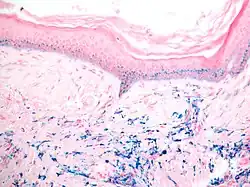

Progressive blaugraue Verfärbungen der Haut werden nach chronischer Aufnahme von Silberverbindungen (z. B. Silbernitrat, Silberiodid) bzw. kolloidalem Silber beobachtet. Man unterscheidet generalisierte (Argyrie) und lokalisierte (Argyrose) Formen. Bevorzugt sind auch hier lichtexponierte Hautareale betroffen. Lichtmikroskopisch zeigen sich kleine rundliche, braunschwarze granulierte Ablagerungen im Bereich der Basalmembran des Haarfollikelepithels.[14]